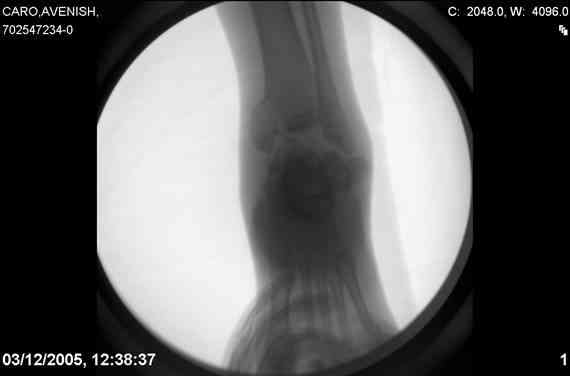

ya by popytalsya sobrat talus anatomichno,seichas pozdno operirovat

iz za oteka,po etomy distrakziya apparatom budet optmalna.Posyalu vam

podobyai moi sluchai.